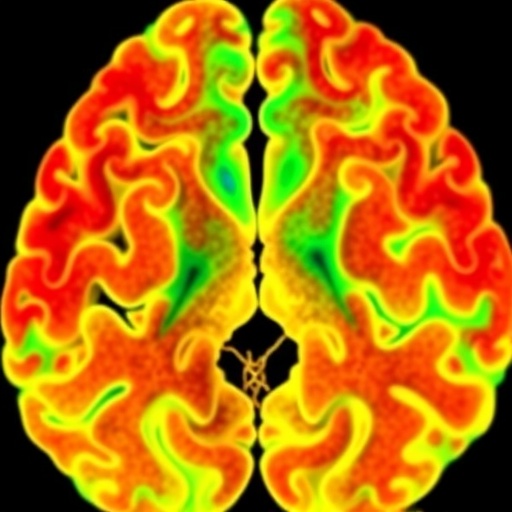

Proteogenomics Uncovers Medulloblastoma Progression Subtypes

In a groundbreaking study published in Experimental & Molecular Medicine, a team of researchers has unveiled a comprehensive proteogenomic map...